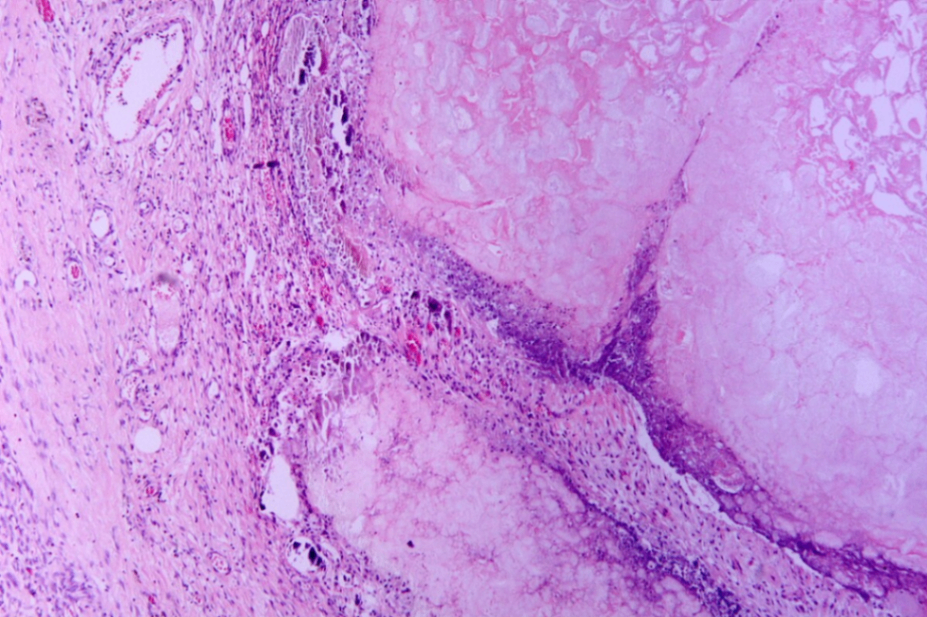

3) 조직학적 소견

지방 괴사 (fat necrosis)

- mesentery의 saponification: 췌장 주위 또는 장간막의 중성지방이 괴사되면서 유리된 지방산이 칼슘과 결합하여 chalky-white한 석회화 침착 형성

• 급성 염증세포 침윤

Tryptic fat tissue necrosis in severe pancreatitis, Wikimedia Commons